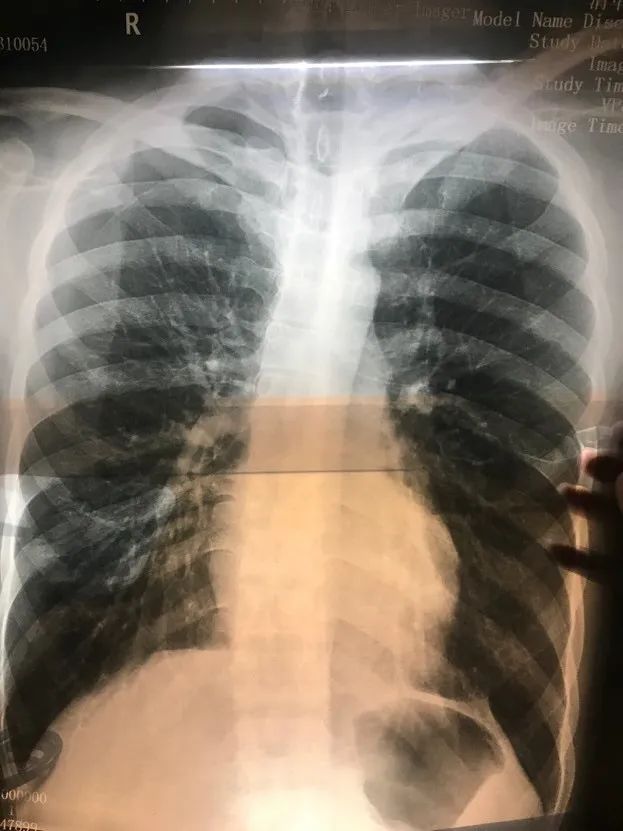

当时小山的胸片

图片来自受访者

医生看了胸片后严肃指出,胸腔里有明显的积液,很可能是血;而如果是血,情况就相当危急,必须当晚立刻进行手术。